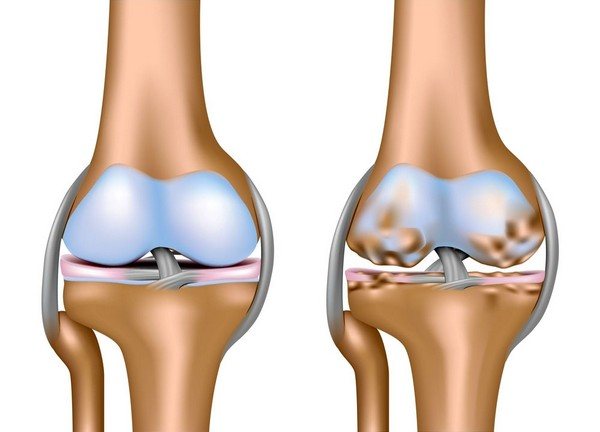

На начальном этапе развития заболевания повреждается хрящевая прослойка, выстилающая поверхности костей. Она истончается, уплотняется, перестает выполнять свою основную амортизирующую функцию. Теперь хрящ не гладкий и упругий, а шершавый, с множеством радиальных трещин на поверхности. При смещении образующих сустав костей хрящевые структуры цепляются друг за друга, что приводит к еще большему их разрушению.

Постепенно деформируются костные поверхности, которые разрастаются с образованием острых наростов — остеофитов. Костные шипы при смещении травмируют мягкие ткани, провоцируя развитие воспалительного процесса. В него вовлекаются синовиальная оболочка, суставная сумка, связки, сухожилия.

Коленного сустава

Артрозо-артриту предшествует гонартроз — дегенеративно-дистрофическое заболевание суставов.

Его течение постепенно осложняется воспалением соединительнотканных структур. Хрящевые поверхности бедренной, большеберцовой кости и надколенника разрушаются, а затем под воздействием ударных нагрузок деформируются и костные структуры колена. Человек испытывает боли при ходьбе, а на конечной стадии не может полноценно опереться на стопу.

- Для артроза коленного сустава характерна быстрая деформация. Разрушение хрящевой ткани при постоянных нагрузках на сустав приводит к появлению шипов, остеофитов, наростов. Колено постепенно перестает сгибаться, а отек и сильная боль мешают наступать на ногу.